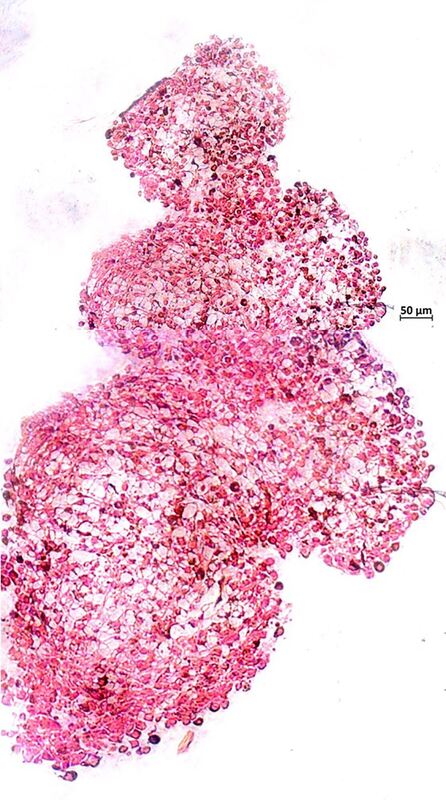

Alternativen zu Tierversuchen Kein Tierversuch, wenn es eine Alternative gibt Diese Selbstverpflichtung gehört nicht nur zu den Leitlinien der Universität Hohenheim, sie ist auch eine gesetzliche Vorschrift. The purpose of this practical guide is to inform you about your obligations to avoid unnecessary testing on vertebrate animals, yet still ensure that you have sufficient information. 3RCC fördert Alternativen zu Tierversuchen In Bern werden drei Gruppen finanziert, die humanbasierte InvitroModelle entwickeln, um Krebserkrankungen, Lungenfibrose und den Austausch von Medikamenten zwischen Mutter und Kind zu untersuchen.

Alternativen zu Tierversuchen gesucht Denn Mäuse, Frösche und Co teilen einige Zelleigenschaften und genetische Anlagen mit dem menschlichen Organismus Die damit gewonnen Erkenntnisse sind oft wertvoll, aber nicht immer auf den Menschen übertragbar und kaum mit dem Tierwohl vereinbar. >>Alternativen zu Tierversuchen >>Grundlagenforschung und Ergebnisse >>Wissenschaftliche Erfolge >>Das 3RPrinzip >>Tierversuche und Ethik >>Zahlen und Fakten >>Belastung von Versuchstieren >>Tierarten in der Forschung >>Forschungsgebiete mit Tierversuchen Über uns. 3RCC fördert Alternativen zu Tierversuchen In Bern werden drei Gruppen finanziert, die humanbasierte InvitroModelle entwickeln, um Krebserkrankungen, Lungenfibrose und den Austausch von Medikamenten zwischen Mutter und Kind zu untersuchen.